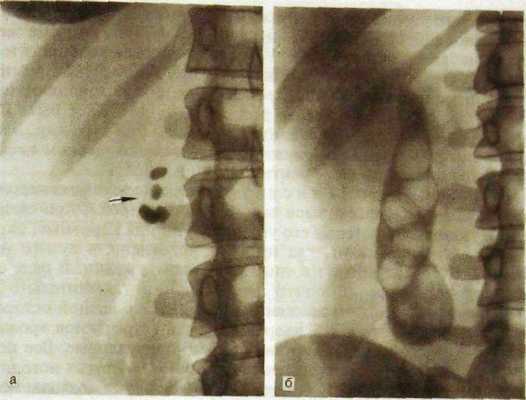

На обычных рентгенограммах желчные камни можно распознать только в том случае, если они содержат отложения извести (рис. III. 145). Остальные камни выявляют при холецистографии, если пузырный проток проходим и контрастированная желчь проникает в пузырь. Камни дают дефекты в тени желчного пузыря. Число, величина и форма дефектов зависят от числа, величины и формы камней. Четко обнаруживаются камни при КТ. С развитием сонографии холецистография, бывшая основным методом выявления камней в пузыре, утратила свое значение.

Ряс. III. 145. Желчные камни.

а — рентгенограмма: выявляются камни, содержащие известь (указано стрелкой); б — холецисто-грамма: видны множественные камни в полости желчного пузыря.